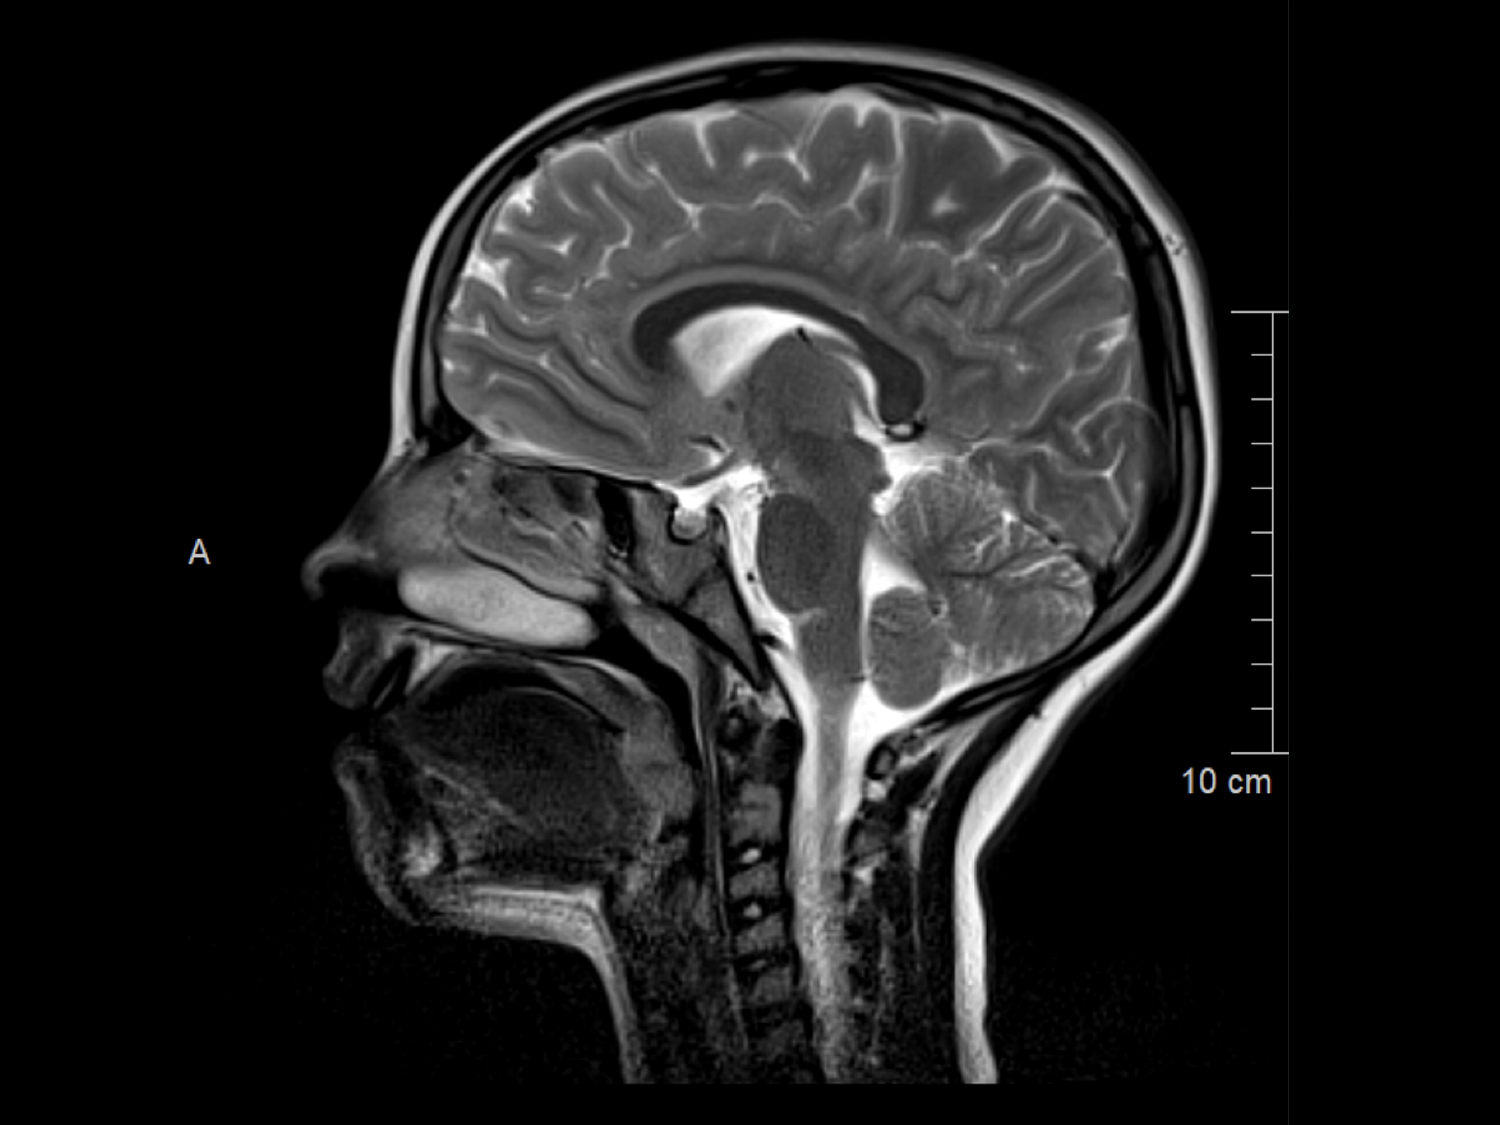

„MRT“ steht für Magnet­resonanz­tomographie, auch bekannt als Kernspin­tomographie. Es ist ein bildgebendes Verfahren, das Magnetfelder und Radiowellen verwendet, um detaillierte Schnittbilder des Körpers zu erzeugen.

Im Gegensatz zu Röntgenstrahlen oder CT-Scans, die ionisierende Strahlung verwenden, nutzt die MRT starke Magnetfelder und Radiowellen, um Bilder zu erzeugen. Dies macht die MRT zu einem besonders sicheren Verfahren für die Diagnose vieler Erkrankungen und Verletzungen, insbesondere im Bereich der Weichteile wie Gehirn, Rückenmark, Gelenke, Muskeln und Organe.